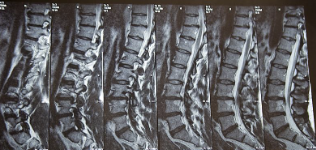

추간판 탈출증 증상 원인 치료방법 등 추간판 탈출증에 대해 정리해드리도록 하겠습니다. 추간판 탈출증은 척추 뼈 사이에 있는 젤리 같은 추간판이 손상되어 신경을 압박하거나 자극하는 질환입니다. 이 질환은 통증, 저림감, 무감각, 근력 저하 등의 증상을 유발할 수 있으며, 특히 요추 부위에서 가장 흔하게 발생합니다. 추간판 탈출증의 원인은 다양하지만, 대부분은 척추의 퇴행성 변화나 반복적인 외상으로 인해 발생합니다. 이 글에서는 추간판 탈출증의 증상과 치료 방법에 대해 알아보겠습니다.

추간판 탈출증의 증상은 탈출된 디스크의 위치와 크기, 그리고 압박되는 신경의 종류에 따라 다르게 나타납니다. 가장 흔한 증상은 다음과 같습니다.